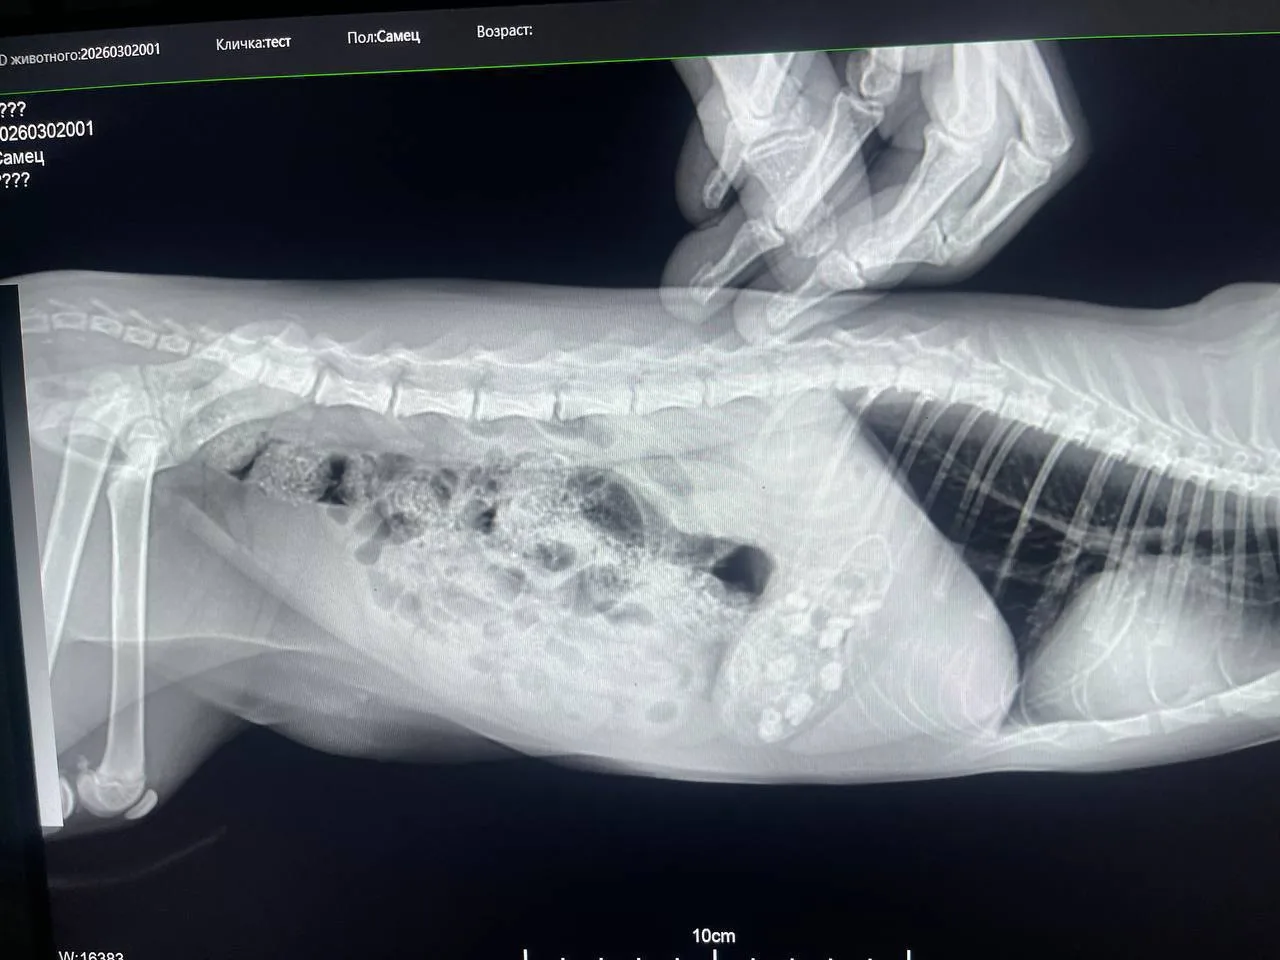

В госветклинику обратились владельцы 4-месячной кошечки по кличке Дюна. Животное чувствовало себя плохо, и хозяева предположили, что питомец съел остатки колбасы. Рентген подтвердил опасения: в желудке обнаружилось 9 инородных предметов.

К сожалению, консервативная терапия не помогла. Врачам пришлось провести сложную операцию — резекцию желудка. Хирурги извлекли 9 металлических скрепок от колбасы и полиамидную оболочку. Сейчас состояние Дюны стабилизировалось, она идет на поправку.